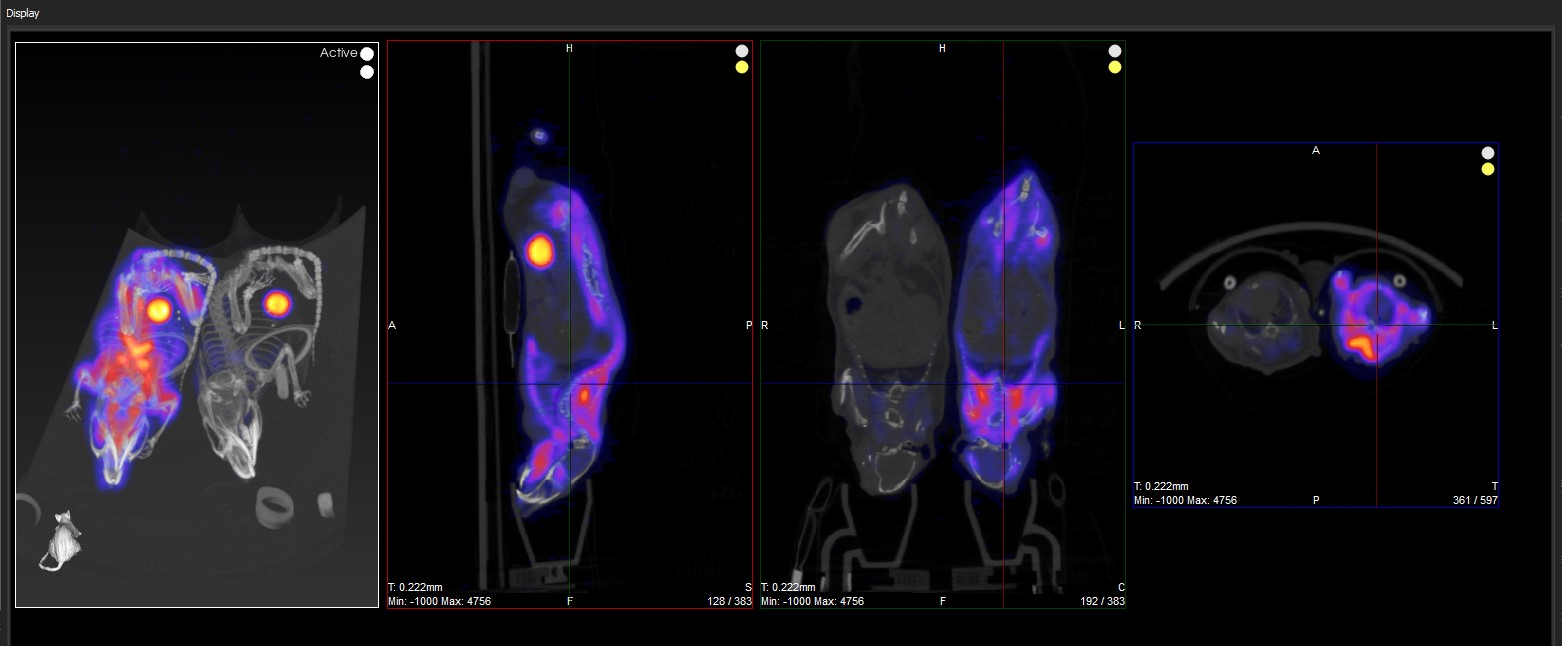

In the example image below, the transversal view is the active view. The ← and → keys move the crosshairs towards the L (left side) and R (right side) in the transversal slice, respectively. Moving through the object to the left or right steps through the sagittal plane of the object; thus, the sagittal slice changes.

The ↑ and ↓ keys will move the crosshair towards P (posterior side) and A (anterior side). Both these sides are also visible in the sagittal slice of the object (rotated 90-degrees). Using the ↑,↓ keys in the transversal plane will shift the vertical crosshair in the sagittal plane, and step through the coronal views of the object.